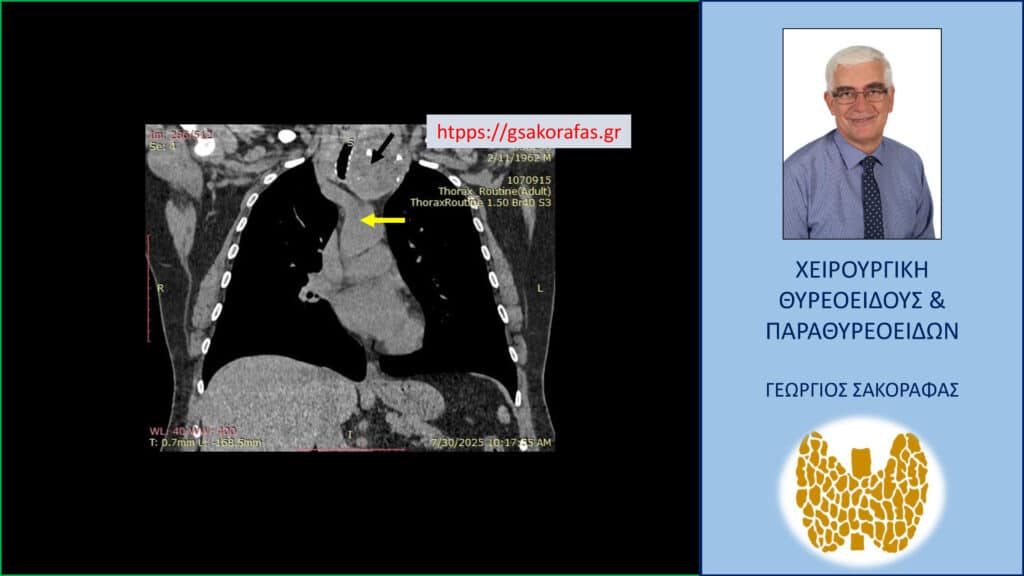

Σε επιλεγμένους ασθενείς μπορεί να χρειαστεί να γίνει αξονική ή μαγνητική τομογραφία, όπως για παράδειγμα όταν υπάρχει κατάδυση στο μεσοθωράκιο για την αξιολόγηση του βάθους στο οποίο εκτείνεται μέσα στον θώρακα η βρογχοκήλη.